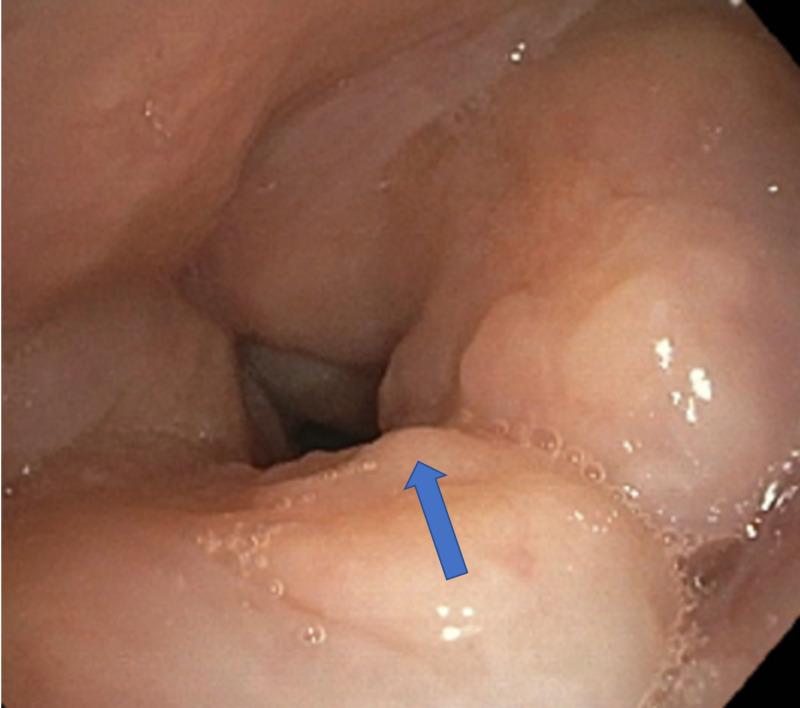

Historically associated with poor prognosis seen in advanced disease, laryngeal tuberculosis (LTB) now represents only 1% of all cases of tuberculosis (TB). The incidence of LTB has decreased drastically with the introduction of anti-tubercular drugs. LTB can be primary or secondary to pulmonary tuberculosis. LTB can mimic laryngeal cancer. We present a case of primary laryngeal TB with descending tracheobronchial spread in an immunocompetent 71-year-old female who developed progressive dysphonia over several months with unintentional weight loss and non-productive cough. Non-contrast enhanced computed tomography (CT) revealed clustering of subcentimeter stellate nodules in the right upper lung field with an enlarging ground-glass opacity in the right lower lung but did not show structural abnormalities within the neck. Positron emission tomography (PET) showed pathologic fluorodeoxyglucose (FDG) uptake within the larynx and trachea with extension into the left mainstream bronchus as well as the proximal left upper and lower lobe bronchi. Diffuse standardized uptake value (SUV) was greatest in the larynx (20.5). Polymerase chain reaction (PCR) on bronchoscope sputum specimen confirmed Mycobacterium tuberculosis. Findings were consistent with primary laryngeal TB with endobronchial extension. She was started on a four-drug regimen comprising of isoniazid, rifampin, ethambutol, and pyrazinamide with a good response. Her close contacts were treated as well. This case highlights the unusual spread of primary laryngeal TB in an immunocompetent host. Early diagnosis can limit adverse complications and unnecessary exposure to healthcare workers. To our knowledge, this is the first case of primary LTB with proximal spread to the tracheobronchial and pulmonary tuberculosis.

喉结核(LTB)在历史上与晚期疾病的不良预后相关,如今在所有结核病(TB)病例中仅占1%。随着抗结核药物的引入,LTB的发病率已大幅下降。LTB可为原发性,也可为继发型肺结核。LTB可酷似喉癌。我们报告一例原发性喉结核病例,该病例发生于一名免疫功能正常的71岁女性,病变呈气管支气管下行播散,患者在数月内逐渐出现进行性声音嘶哑、体重意外减轻及干咳。非增强计算机断层扫描(CT)显示右上肺野有多个小于1厘米的星状结节聚集,右下肺有一个增大的磨玻璃影,但颈部未见结构异常。正电子发射断层扫描(PET)显示喉部和气管内有病理氟脱氧葡萄糖(FDG)摄取,病变延伸至左主支气管以及左肺上叶和下叶近端支气管。弥漫性标准化摄取值(SUV)在喉部最大(20.5)。支气管镜痰液标本聚合酶链反应(PCR)证实为结核分枝杆菌。检查结果与原发性喉结核伴支气管内播散一致。她开始接受异烟肼、利福平、乙胺丁醇和吡嗪酰胺组成的四联治疗方案,反应良好。她的密切接触者也接受了治疗。该病例突出了原发性喉结核在免疫功能正常宿主中的不寻常播散。早期诊断可限制不良并发症以及医护人员不必要的暴露。据我们所知,这是首例原发性LTB近端播散至气管支气管和肺结核的病例。